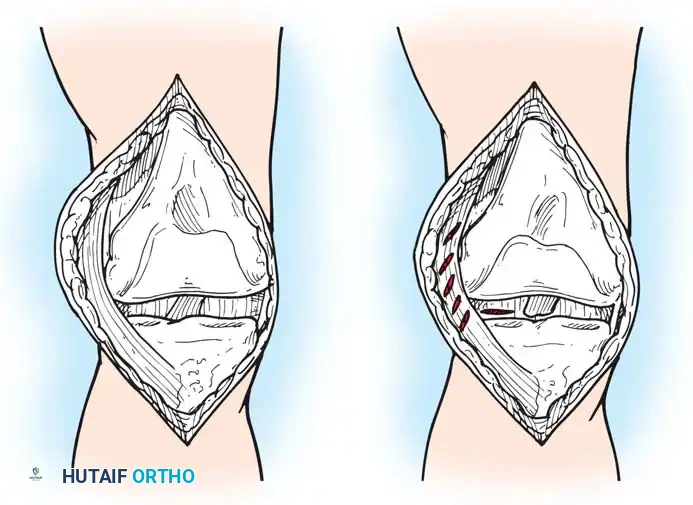

The Medial Parapatellar Retinacular Approach

The standard and most versatile retinacular incision in TKA is the medial parapatellar approach. It provides extensile exposure and is suitable for nearly all primary and revision scenarios.

- Make the skin incision with the knee in flexion. This allows the subcutaneous tissue to fall medially and laterally, naturally improving exposure.

- If a preexisting anterior scar is present in a usable position, incorporate it. If multiple previous incisions exist, choose the most lateral usable incision. The blood supply to the skin of the anterior knee predominantly arises from the medial side; violating this principle risks catastrophic skin necrosis.

- Ensure the skin incision is long enough to avoid excessive tension during retraction.

- Keep the medial skin flap as thick as possible by maintaining dissection just superficial to the extensor mechanism.

- Extend the retinacular incision proximally along the length of the quadriceps tendon, leaving a 3- to 4-mm cuff of tendon on the vastus medialis to facilitate robust closure.

- Continue the incision around the medial border of the patella, extending 3 to 4 cm onto the anteromedial surface of the tibia, parallel to the medial border of the patellar tendon.

- Expose the medial side of the knee by subperiosteally elevating the anteromedial capsule and the deep medial collateral ligament (MCL) off the tibia, extending to the posteromedial corner of the knee.

- Extend the knee and evert the patella. This allows for a routine release of the lateral patellofemoral plicae. In obese patients, if eversion is difficult, develop the lateral subcutaneous flap further so the patella can be everted underneath this tissue without avulsing the patellar tendon.